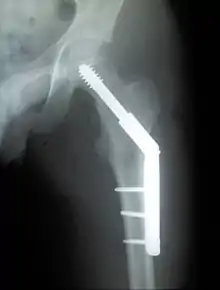

Dynamic hip screw (DHS) or Sliding Screw Fixation is a type of orthopaedic implant designed for fixation of certain types of hip fractures which allows controlled dynamic sliding of the femoral head component along the construct. It is the most commonly used implant for extracapsular fractures of the hip,[1] which are common in older osteoporotic patients. There are 3 components of a dynamic hip screw, including a lag screw (inserted into the neck of the femur), a sideplate and several cortical screws (fixated into the proximal femoral shaft). The idea behind the dynamic compression is that the femoral head component is allowed to move along one plane; since bone responds to dynamic stresses, the native femur may undergo primary healing: cells join along boundaries, resulting in a robust joint requiring no remodeling.